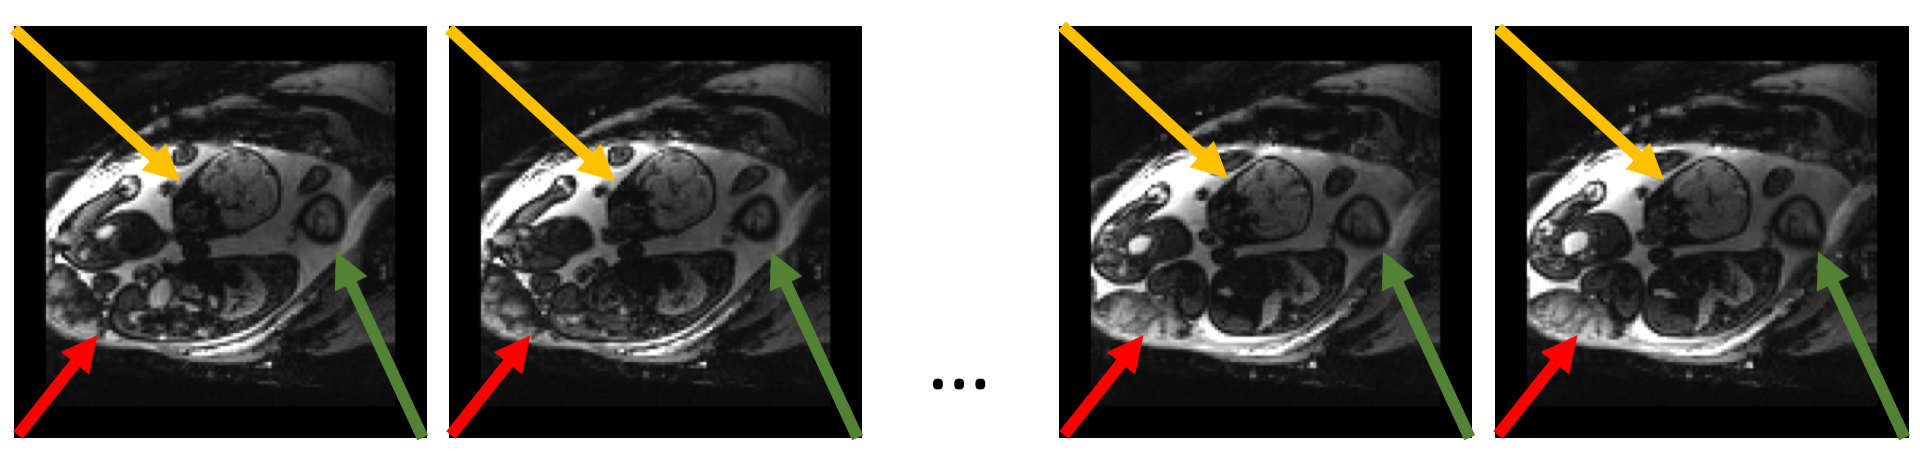

In-utero blood oxygenation level dependent (BOLD) magnetic resonance imaging (MRI) is a promising imaging tool for studying functional dynamics of placenta and fetal organs [1, 2, 3, 4]. Changes in fetal and placental oxygenation levels with maternal hyperoxygenation can be used for charactering and detecting placental dysfunction [5]. Temporal MRI data suffers from serious motion artifacts due to maternal respiration, unpredictable fetal movement, and signal non-uniformities [6], as illustrated in Fig. 1. Different types of motion are presented in these MRI time series. The fetal brains move as rigid objects with a wide range of motion; the placenta moves more locally and deforms non-rigidly. In our study, the image series include about 500 volumes (frames) that are analyzed to study fetal and placental physiology.